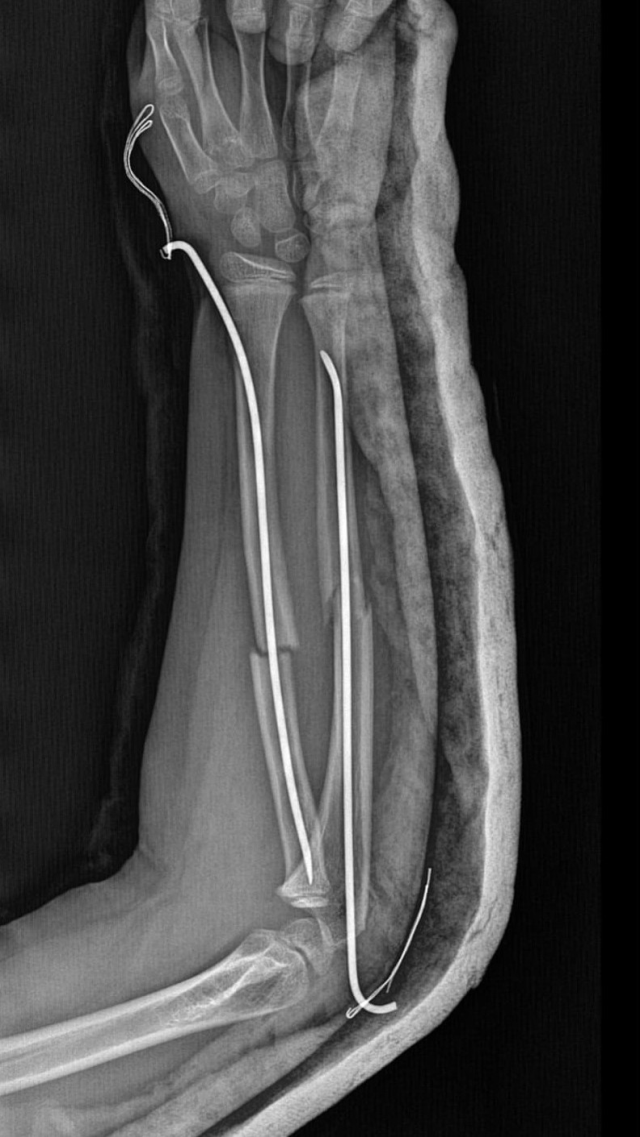

İstanbul'un Büyükçekmece ilçesinde Tepecik'te bulunan bir ilkokulda geçtiğimiz ay korkunç bir olay yaşandı. İddiaya göre 8 yaşındaki Y.K.Ş. okulda bir süredir kendisini rahatsız eden 9 yaşındaki çocuk tarafından darp edilerek kolu ikiye katlandı. Y.K.Ş.'nin 2'ye katlanan kolu 2 ayrı yerinden kırıldı.

Öğretmenler Y.K.Ş.'nin ailesini arayarak, 'oğlunuz arkadaşıyla kavga etti duvara çarptı' denildi. Oğlunu okuldan alıp hastaneye götüren anne Songül Gökdemir, oğlunun kolunun 2 ayrı yerinden kırıldığını öğrenip ameliyata alınacağını duyduğunda büyük şok yaşadı.

Konuyla ilgili anne Gökdemir savcılığa giderek şikayetçi oldu. Savcılıktan ise 'söz konusu Suça Sürüklenen Çocuğun yaşının 12'den küçük olduğu gerekçesi ile kovuşturmaya yer yoktur' kararı çıktı. Anne Gökdemir karara itiraz ederken mağdur Y.K.Ş. ise haftalardır okula gidemiyor. Eğitimi aksayan çocuğun 2 hafta sonra ise platinlerinin çıkarılması için yeniden ameliyata gireceği öğrenildi.

Yaşanan olayı anlatan Songül Gökdemir, "Arkadaşlarından darbe aldığını biliyordum. Ayrıca eylül ayından bu yana bir arkadaşının onun kolunu kırmaya çalıştığını söyledi. Ben de 'arkadaşını öğretmene söyle' dedim. Bundan kaçıyordu. O gün de rehber öğretmenine bu arkadaşını şikayet ettiler. Ben işe gittim 1 saat sonra öğretmeni aradı. Oğlunuz arkadaşıyla birbirini itekledi kolunu duvara çarptı gelir misiniz?' dedi. Kendi imkanımla hastaneye götürdüm. Okula gittiğimde de oğlum derste oturuyordu. Öğretmen ders işliyordu ambulans çağırılmamış. Hastanede kolunda 2 tane kırık olduğunu acilen de ameliyata girmesi gerektiğini öğrendim. 3 gün sonra ameliyata alındı. Kolundaki platinlerden dolayı her gün pansumanı var. 2 hafta sonra tekrar ameliyatı var" dedi.